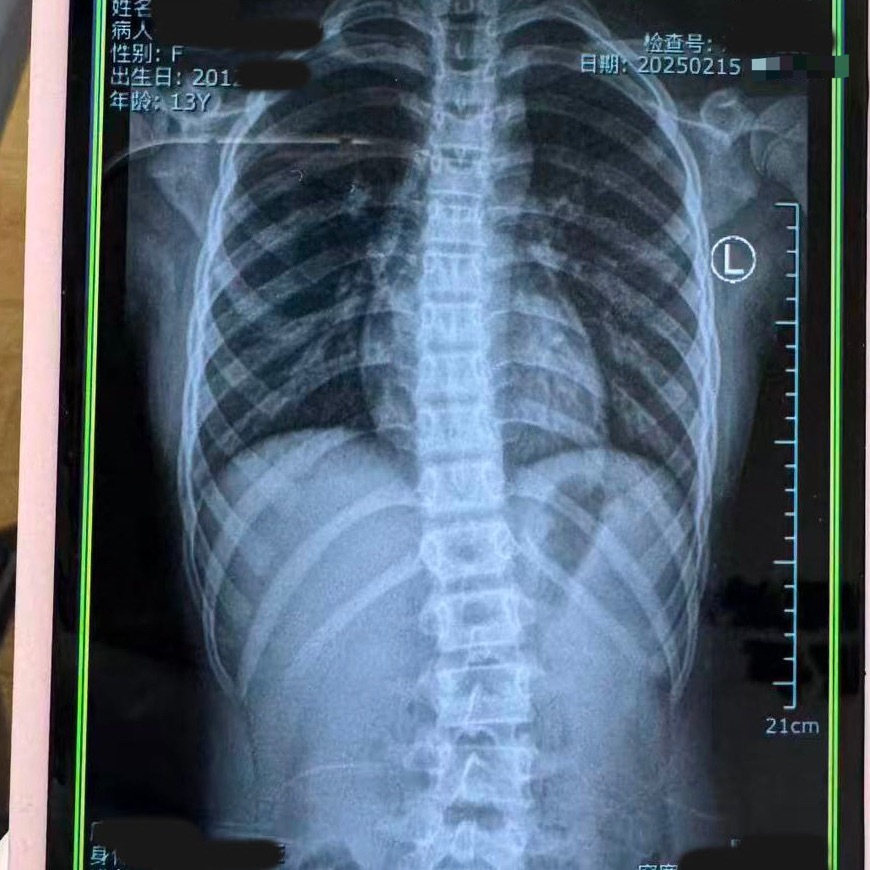

脊柱侧弯 来看个对比——13岁的小姑娘,脊柱侧弯,康复训练3个月的前后变化。

对于脊柱侧弯,成年人很难发生骨骼形态上的变化,但对于正发育期的孩子,及时介入➕坚持康复,就会有很好的改善[思考][思考]锐博康复